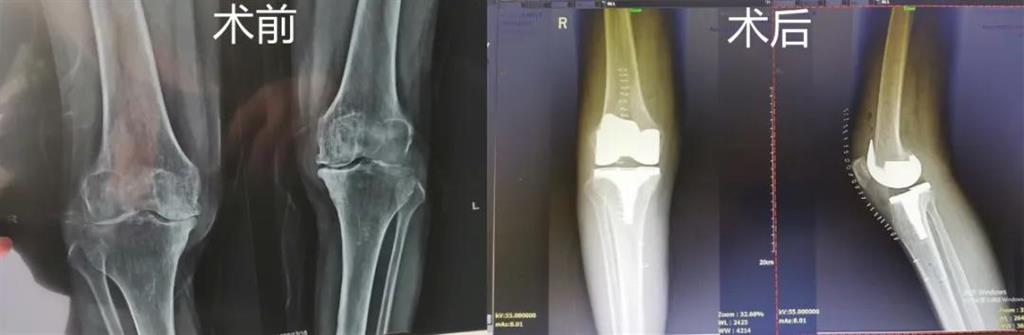

最近,和平國際醫(yī)院骨科中心開展了一項(xiàng)新業(yè)務(wù)——計(jì)算機(jī)導(dǎo)航膝關(guān)節(jié)置換術(shù),而年邁78歲的李奶奶則幸運(yùn)地成為該手術(shù)的首個受益者。這也是溫州地區(qū)率先將骨科傳統(tǒng)手術(shù)與計(jì)算機(jī)導(dǎo)航系統(tǒng)相結(jié)合應(yīng)用的成功案例,也是和平國際醫(yī)院骨科中心在膝關(guān)節(jié)置換術(shù)方面所取得的一次重大突破!

和平國際醫(yī)院副院長、骨科中心主任劉丹在診斷后發(fā)現(xiàn),老人雙側(cè)膝關(guān)節(jié)患有骨性關(guān)節(jié)炎,右側(cè)膝關(guān)節(jié)較為嚴(yán)重,而且關(guān)節(jié)磨損嚴(yán)重,關(guān)節(jié)間隙基本消失。

經(jīng)過進(jìn)一步檢查后,劉丹帶領(lǐng)團(tuán)隊(duì)在計(jì)算機(jī)導(dǎo)航系統(tǒng)的輔助下,為老人實(shí)施了右側(cè)全膝關(guān)節(jié)置換手術(shù)。術(shù)中出血明顯減少,術(shù)后疼痛腫脹等反應(yīng)輕微,畸形矯正力線恢復(fù)理想,而且功能恢復(fù)快速,術(shù)后四天就可以下地行走。

據(jù)劉丹主任介紹,計(jì)算機(jī)導(dǎo)航膝關(guān)節(jié)置換術(shù)可以避免打開股骨髓腔,從而明顯減小手術(shù)創(chuàng)傷,減少術(shù)中出血,能夠更精準(zhǔn)地從三維角度調(diào)整手術(shù)截骨方向,恢復(fù)肢體對線,并能進(jìn)行精確的軟組織平衡,從而使患者獲得良好的術(shù)后功能恢復(fù)。